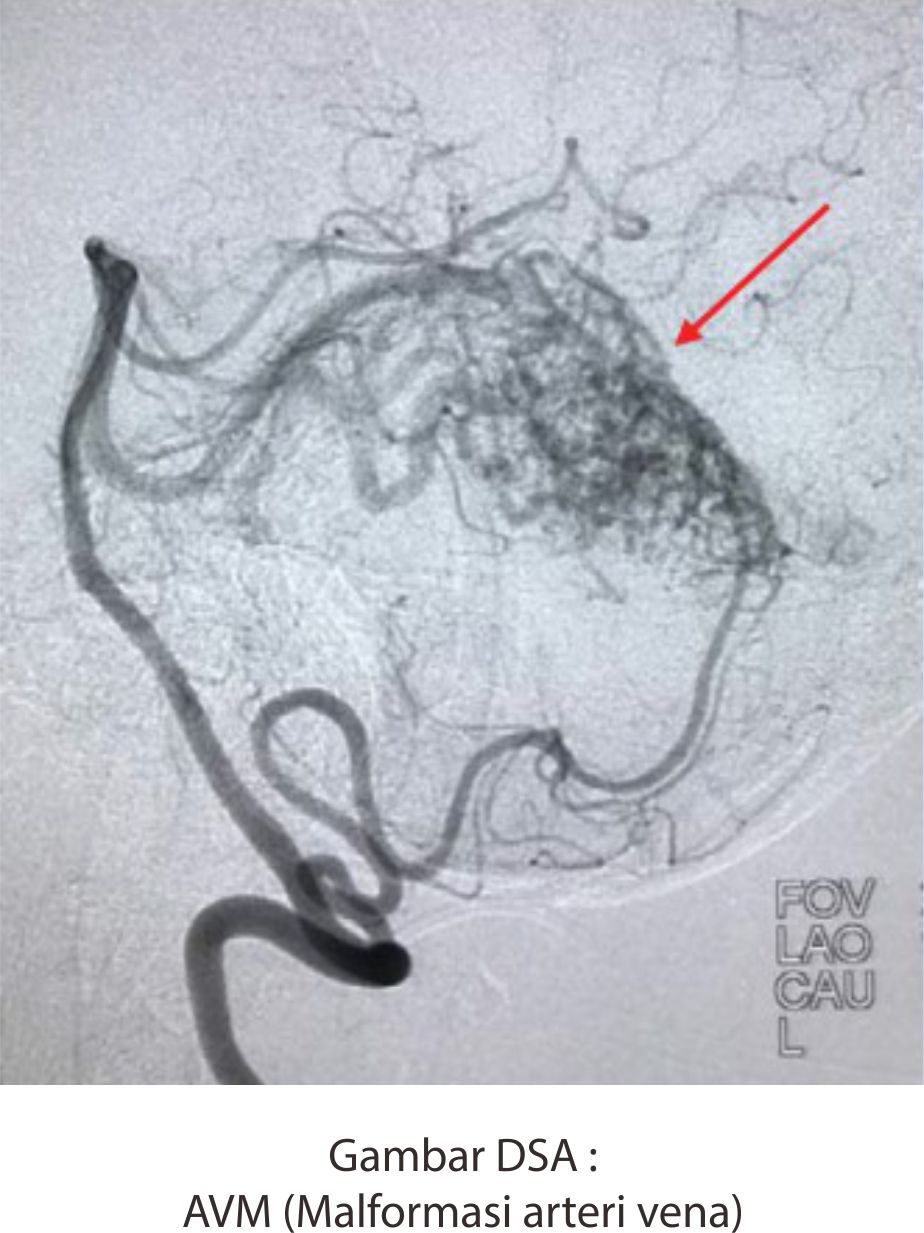

- Pasien dengan perdarahan di otak dan diduga disebabkan adanya AVM (malformasi pembuluh darah) yang pecah, seringkali usia muda, lokasi perdarahan di kortikal, tidak ada riwayat darah tinggi, perdarahan berulang di daerah yang sama.

AVM / AVF (malformasi arteri vena), feeder arteri, vena drainase.